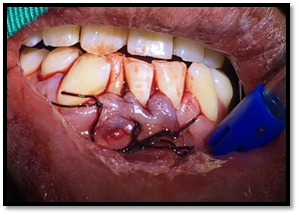

Paciente de sexo masculino de 32 años de edad, Asintomático, en la exploración clínica intraoral se observa ausencia del órgano dentario Nº 4, 2. No hay la presencia de cambios de coloración en la mucosa del sector anterior del cuerpo de la mandíbula, a la palpación no refiere dolor.

Imagen 1. Fotografías intraorales

Incisión: Neumann Parcial con bisturí, hoja de bisturí # 15 con un mango de bisturí #3, con la descarga o liberatríz hacia el órgano dentario #3.2 hasta distal del órgano dentario # 4.4.

Levantamiento del colgajo: Se realizó el levantamiento de las papilas y el colgajo mucoperióstico.

Imagen 6. Incisión.

Imagen 7. Levantamiento del colgajo.